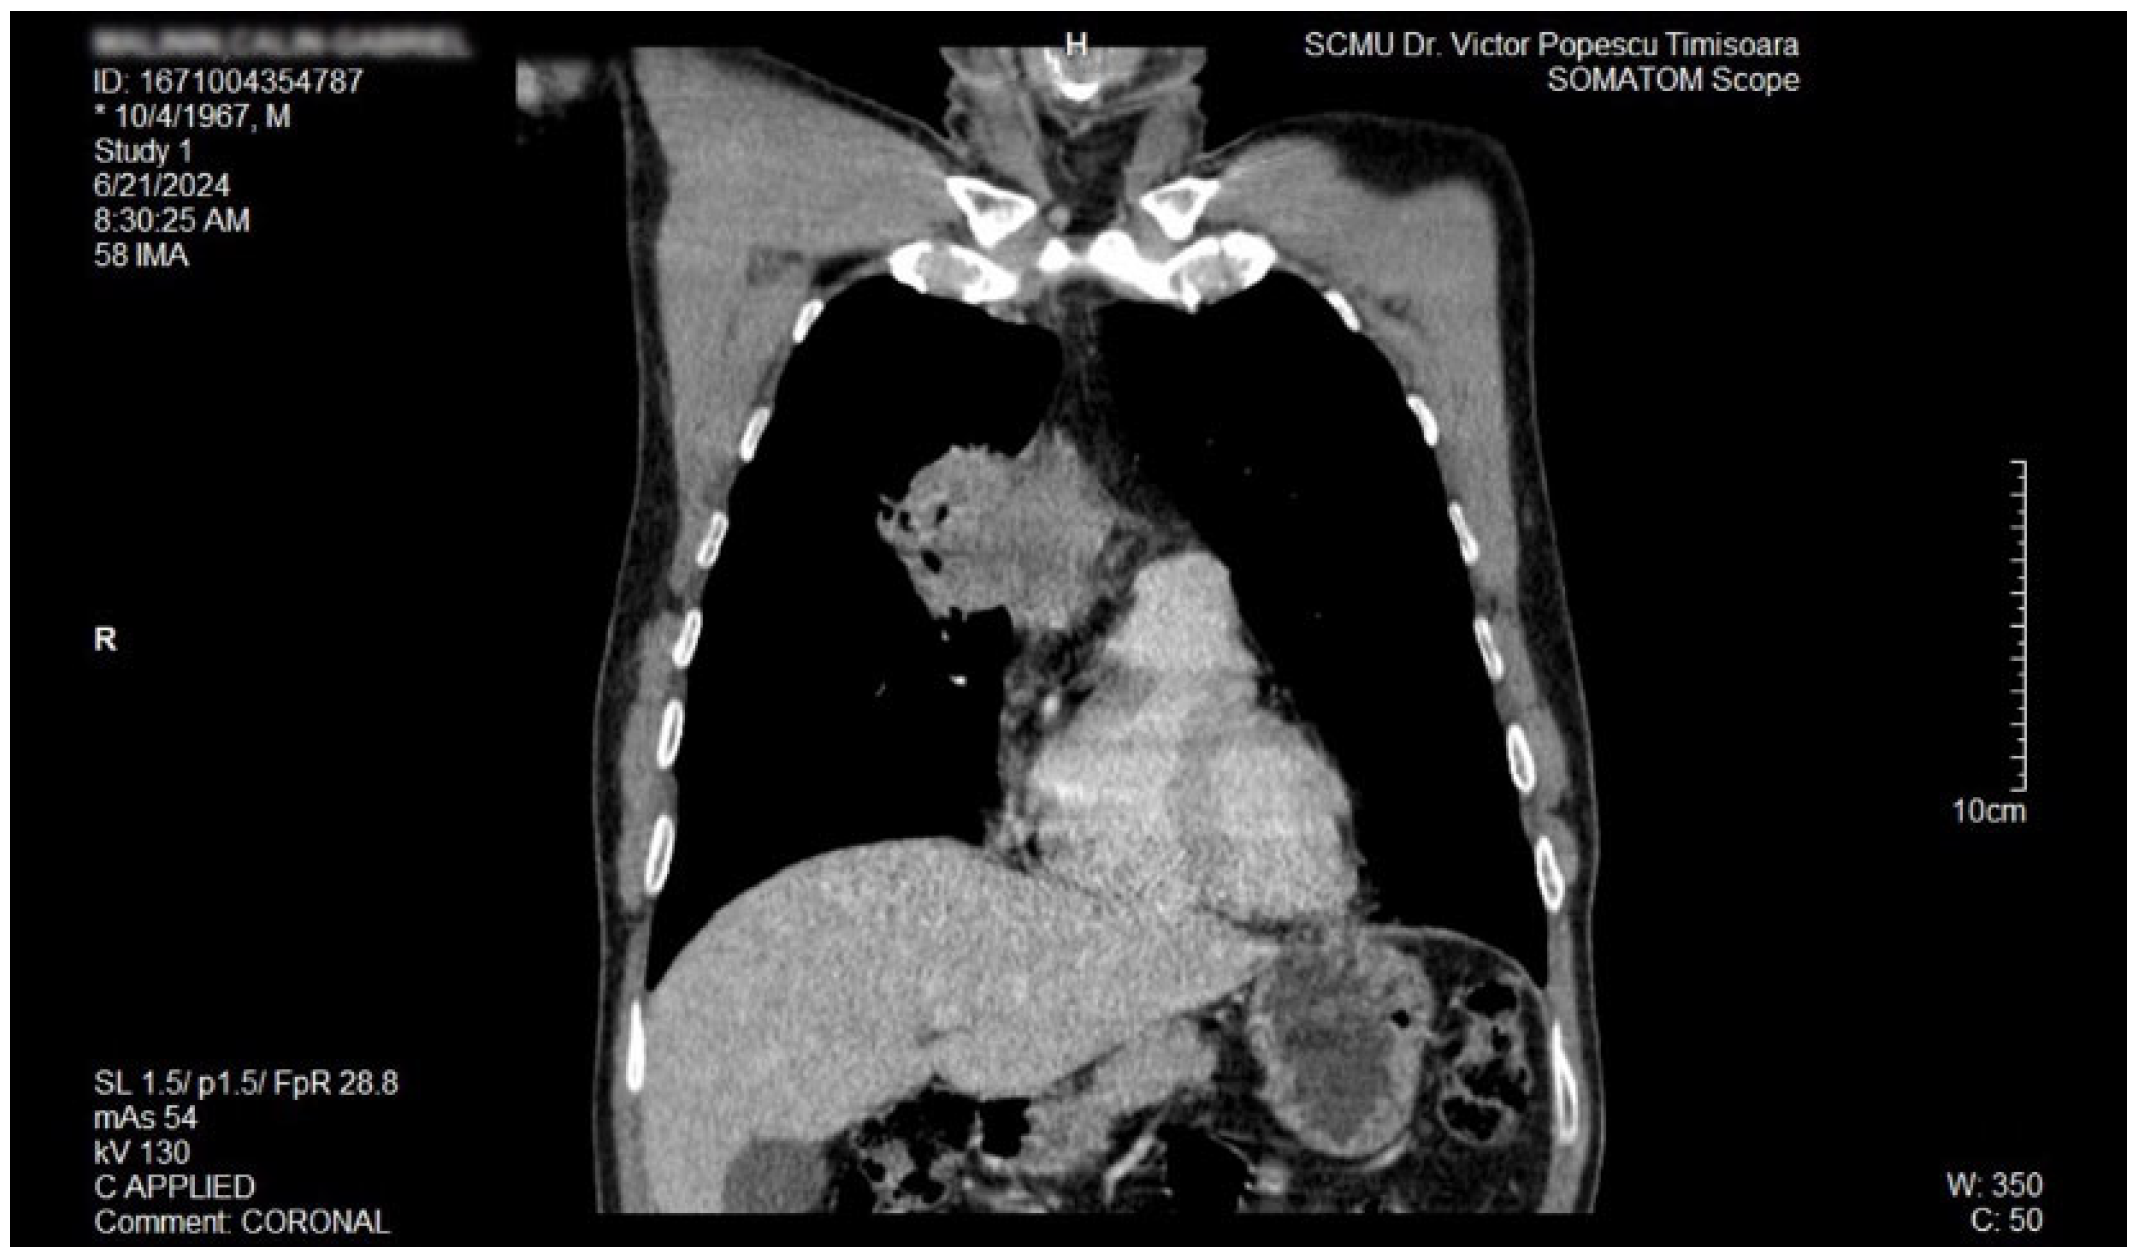

2. Case Report